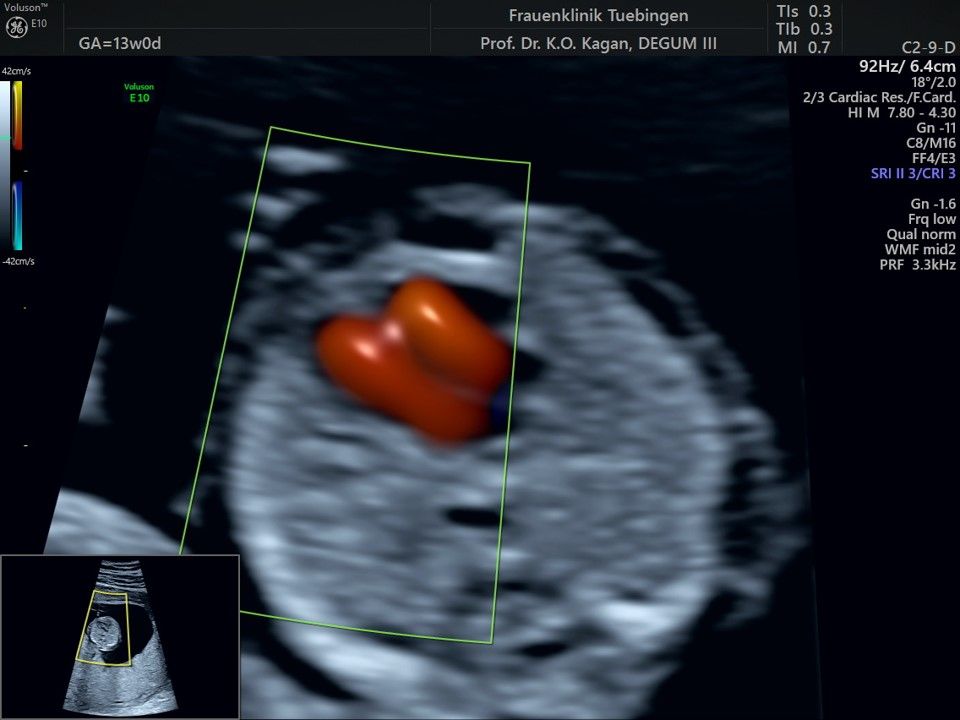

Herz

Das Ergebnis der Ultraschalluntersuchung ist wegweisend. Dabei wird der Fet vermessen, die Organe werden untersucht und die sonographischen Marker zur Risikoberechnung für Chromosomenstörungen werden beurteilt. Das sind: die Nackentransparenzdicke, Nasenbein sowie der Blutfluss in der rechten Herzhälfte und im Ductus venosus, einem Gefäß in der Leber des Feten.